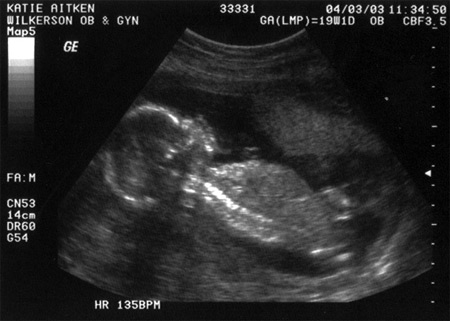

Here is Maeve's sonogram, from when she was the same gestational age: